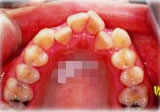

開咬症例

骨格性開咬と診断し、外科的処置を併用して治療。

矯正治療は上下顎歯列を拡大しスペースを作成、非抜歯にて行った。

上顎 上顎 上顎